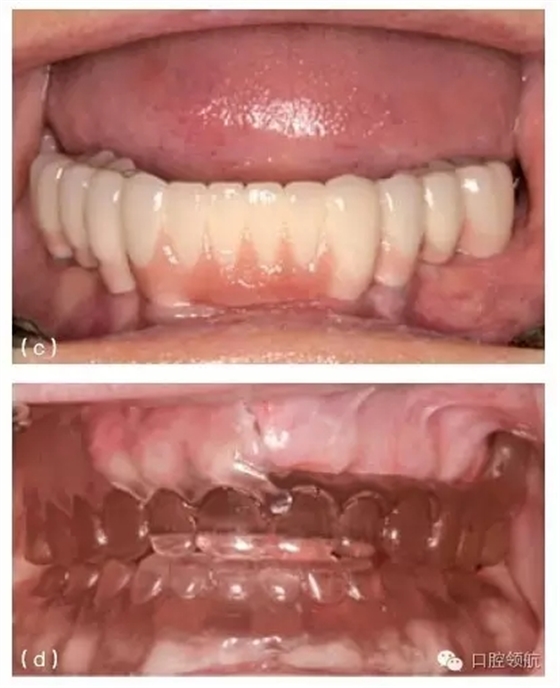

在制訂上頜全口固定義齒的治療計(jì)劃前,必須認(rèn)真考慮修復(fù)體能否向患者提供足夠的唇部支持。建議采用樹脂復(fù)制患者的義齒,或者在蠟型上按理想牙列外形排列牙齒,然后在一側(cè)切去翼板,以模擬全口固定義齒的外形,而在對(duì)側(cè)則保留傳統(tǒng)的可摘覆蓋義齒外形。通過這種方法,可以判斷無翼板的一側(cè)(模擬全口固定義齒)能否支撐起患者的唇部,以便最終確定適合患者的修復(fù)體類型(圖10.35d~f)。這種方法也可以讓患者行使知情決定權(quán),通過觀察左右側(cè)唇部的豐滿狀況,來選擇最終的修復(fù)體類型。有時(shí),上頜全口固定義齒也會(huì)出現(xiàn)美學(xué)并發(fā)癥,表現(xiàn)為患者微笑時(shí),唇部出現(xiàn)一條明顯的線,反映出修復(fù)體在口內(nèi)的狀況。

圖10.35 (a)上頜中切牙周圍的牙齦乳頭充填,形成了良好的軟組織外觀。(b)(a)圖中種植體冠的X線片顯示,相對(duì)修復(fù)體和種植體來說,鄰面牙槽骨處于理想的位置。(c)下頜種植支持式的局部固定義齒,采用牙齦色的烤瓷來改善頸部外觀。(d)復(fù)制的上頜全口義齒的前面觀,一側(cè)的頰側(cè)翼板被去除,以模擬上頜全口固定義齒的外觀。(e)右側(cè)觀唇部的支撐效果。(f)左側(cè)觀唇部的支撐效果。這一側(cè)對(duì)唇部的支撐明顯不如對(duì)側(cè)。